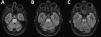

Eleven days after discharge (21 days after the episode of loss of consciousness), the patient visited the emergency department due to right limb weakness, which had progressively worsened over the previous 48 hours. The neurological examination revealed mixed consistency dysphagia, dysarthria, and absent gag reflex bilaterally, with severe right-sided faciobrachiocrural paralysis, mild left-sided crural paresis, and bilateral pyramidal signs. Blood electrolyte levels were normal. She was admitted to the neurology department for assessment. A brain MRI scan revealed a well-delimited area occupying the central part of the pons, which was hypointense on T1-weighted sequences and hyperintense on T2-weighted and FLAIR sequences (Fig. 2A-C). This finding is highly suggestive of pontine osmotic demyelination. The patient started intensive physical therapy during hospitalisation, and continued with the treatment on an outpatient basis. At 3 months of follow-up, she was able to walk unaided, although mild ataxia persisted.